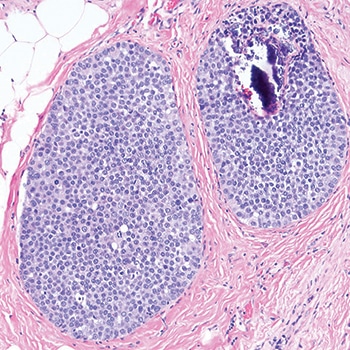

Dr. Schnitt shared a case in which the screening mammogram of a 47-year-old woman exhibited new microcalcifications. He described an image of the core biopsy as clearly showing “an in situ carcinoma composed of a solid proliferation of relatively small cells with low-to-intermediate grade nuclei.” There is “no evidence of lumen formation, no micropapillations, no cribriforming.” (Fig. 1). At somewhat higher power, there’s “a little area of necrosis and a relatively uniform population of cells,” and perhaps some dyshesion (Fig. 2).

A case like this is “really tough to categorize on H&E alone,” Dr. Schnitt said, so the differential diagnosis was DCIS versus LCIS. He showed an image of the E-cadherin staining (Fig. 3). “One way to view this is to say, ‘Wow, it’s positive; therefore it’s DCIS,’ but quite frankly I think it looks a little funny,” he told the audience. “There is clearly membrane staining, but there seems to be a fair amount of cytoplasmic staining as well, which is not typical for DCIS.”